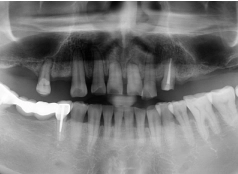

• Tình trạng răng trước đây:Mất nhiều răng ở hàm trên, tiêu xương hàm.

• Bác sĩ chỉ định:Cấy ghép Implant All On 4 hàm trên.

• Implant sử dụng:Implant Mis C1 Đức.

• Răng sứ sử dụng:Răng sứ Titan Mỹ.

• Cấy ghép Implant All On 4 hàm trên